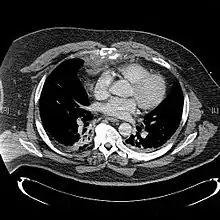

| A displaced sternal fracture as seen on plain X-ray | |